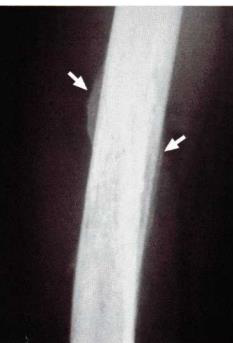

Sobre as reações periosteais, considere a radiografia de fêmur, abaixo:

Trata-se de um paciente com osteomielite do fêmur, caracterizando a reação do tipo:

Quando um processo patológico atinge o osso, ele pode reagir a essa agressão por uma elevação e neo-osteogênese do periósteo, denominada reação periosteal. As reações periosteais podem fornecer indícios importantes sobre o grau de agressividade da lesão à radiografia. Dentre os tipos, quando há em apenas uma camada, denomina-se reação: